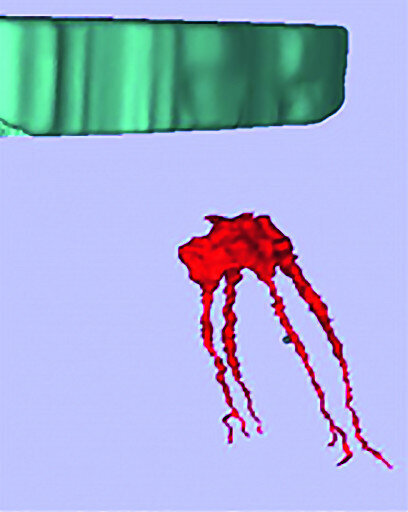

Figs. 11a–c : Depuis la gauche : plan de traitement virtuel pour un accès endodontique guidé par scanner (CT-GEA). La dent à traiter est segmentée par le scanner volumique, des trajets d’accès idéaux sont tracés au travers de la face occlusale de la dent, et un guide de forage CT-GEA est imprimé en 3D.